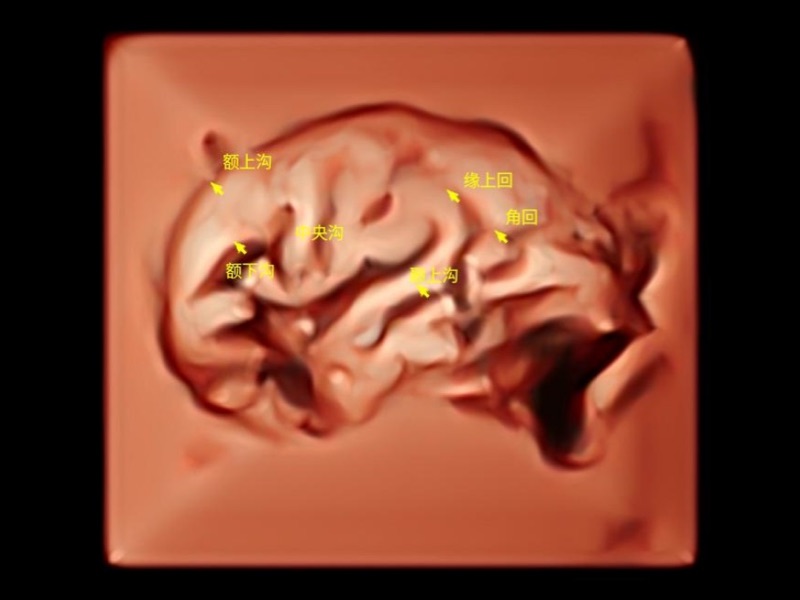

作為開(kāi)立醫(yī)療全新打造的超高端旗艦超聲產(chǎn)品,從探頭抬起喚醒開(kāi)啟掃查到多維探頭發(fā)射接收,通過(guò)先進(jìn)的場(chǎng)成像發(fā)射、自適應(yīng)聚合重建等技術(shù),基于RF Data原始射頻數(shù)據(jù)在圖像生成、高端功能等方面實(shí)現(xiàn)突破,為婦產(chǎn)科、兒科提供全方位臨床解決方案。

獨(dú)有場(chǎng)成像發(fā)射技術(shù)

自適應(yīng)聚合重建技術(shù)

獨(dú)家XPUs混合硬件架構(gòu)

構(gòu)建多維智能生態(tài)